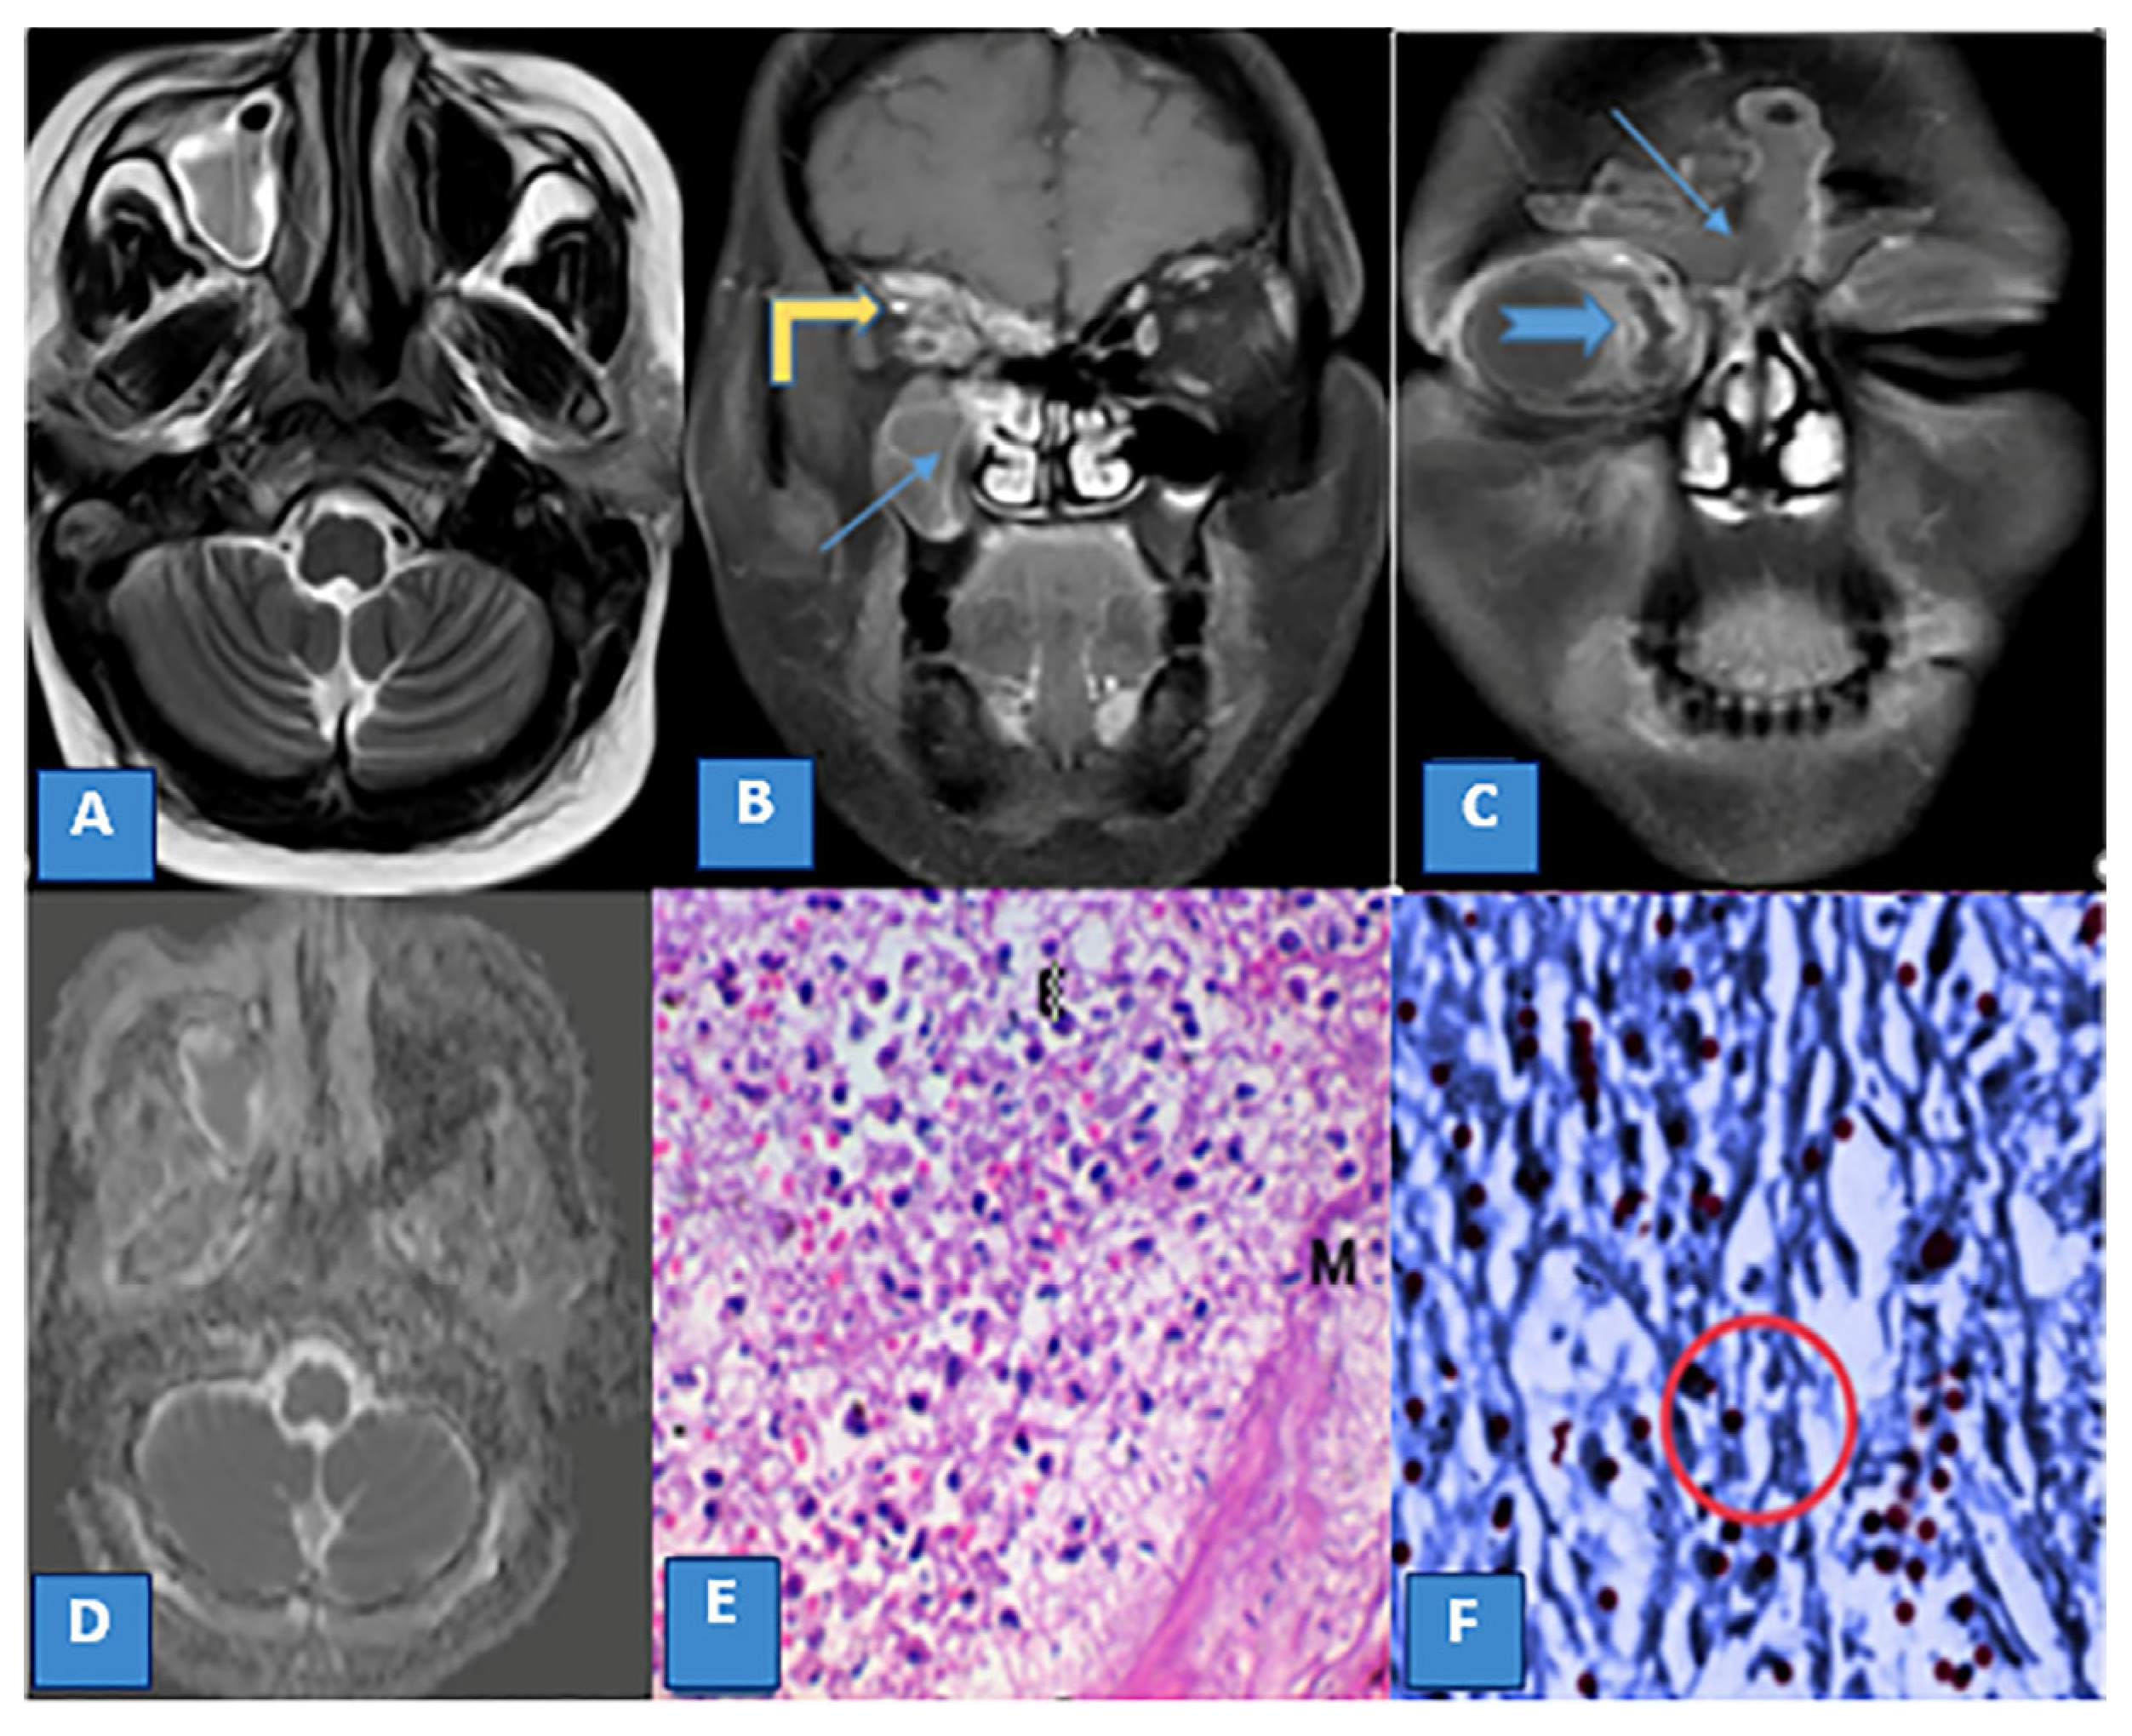

Magnetic Resonance Imaging Features of Rhino-Orbito-Cerebral Mucormycosis in Post-COVID-19 Patients: Radio-Pathological Correlation

3.3. MRI Findings and Signal Characteristics

3.4. Extrasinus Extension

3.5. Histopathological Findings